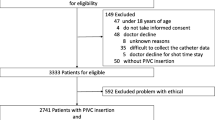

Included in this secondary analysis were 664 adults who required an AC (Fig. 1). Patients were predominately male (n = 449; 68%), aged between 16 and 59 years (n = 346; 52%) and admitted for a medical condition (n = 316, 48%; Table 1). Eighteen percent (n = 118) of patients had a current infection, most commonly respiratory (n = 65; 10%). Seventy-nine percent (n = 524) of patients required mechanical ventilation, with the median ICU length of stay, at time of device insertion 4 days (IQR 3, 4).

Figure 1 Flowchart illustrating how the analysis population evaluated in this secondary analysis was derived from the overall intention-to-treat population of the RSVP trial.